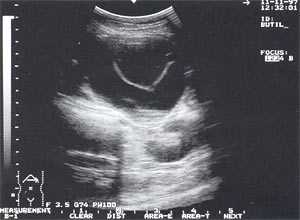

- изменение эхогенности железы: повышение - 85,6% случаев (рис. 2); нормальная - 8,6% случаев; понижение - 5,8% случаев.

Рис. 2. Острый панкреатит, повышение эхогенности поджелудочной железы (по сравнению с эхогенностью печени).